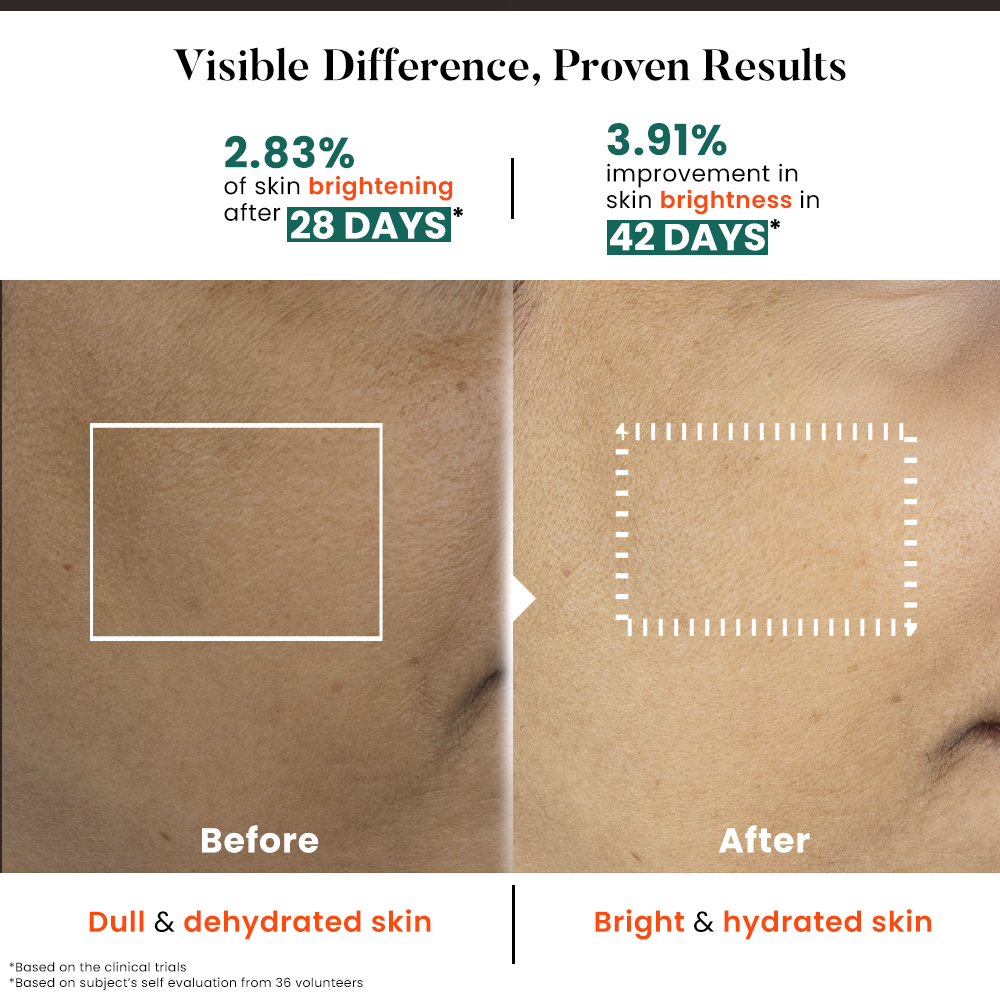

Before

After